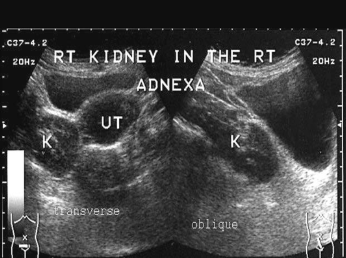

Ectopic Kidney

Having one kidney that is out of its normal position (from birth, failure to ascend).